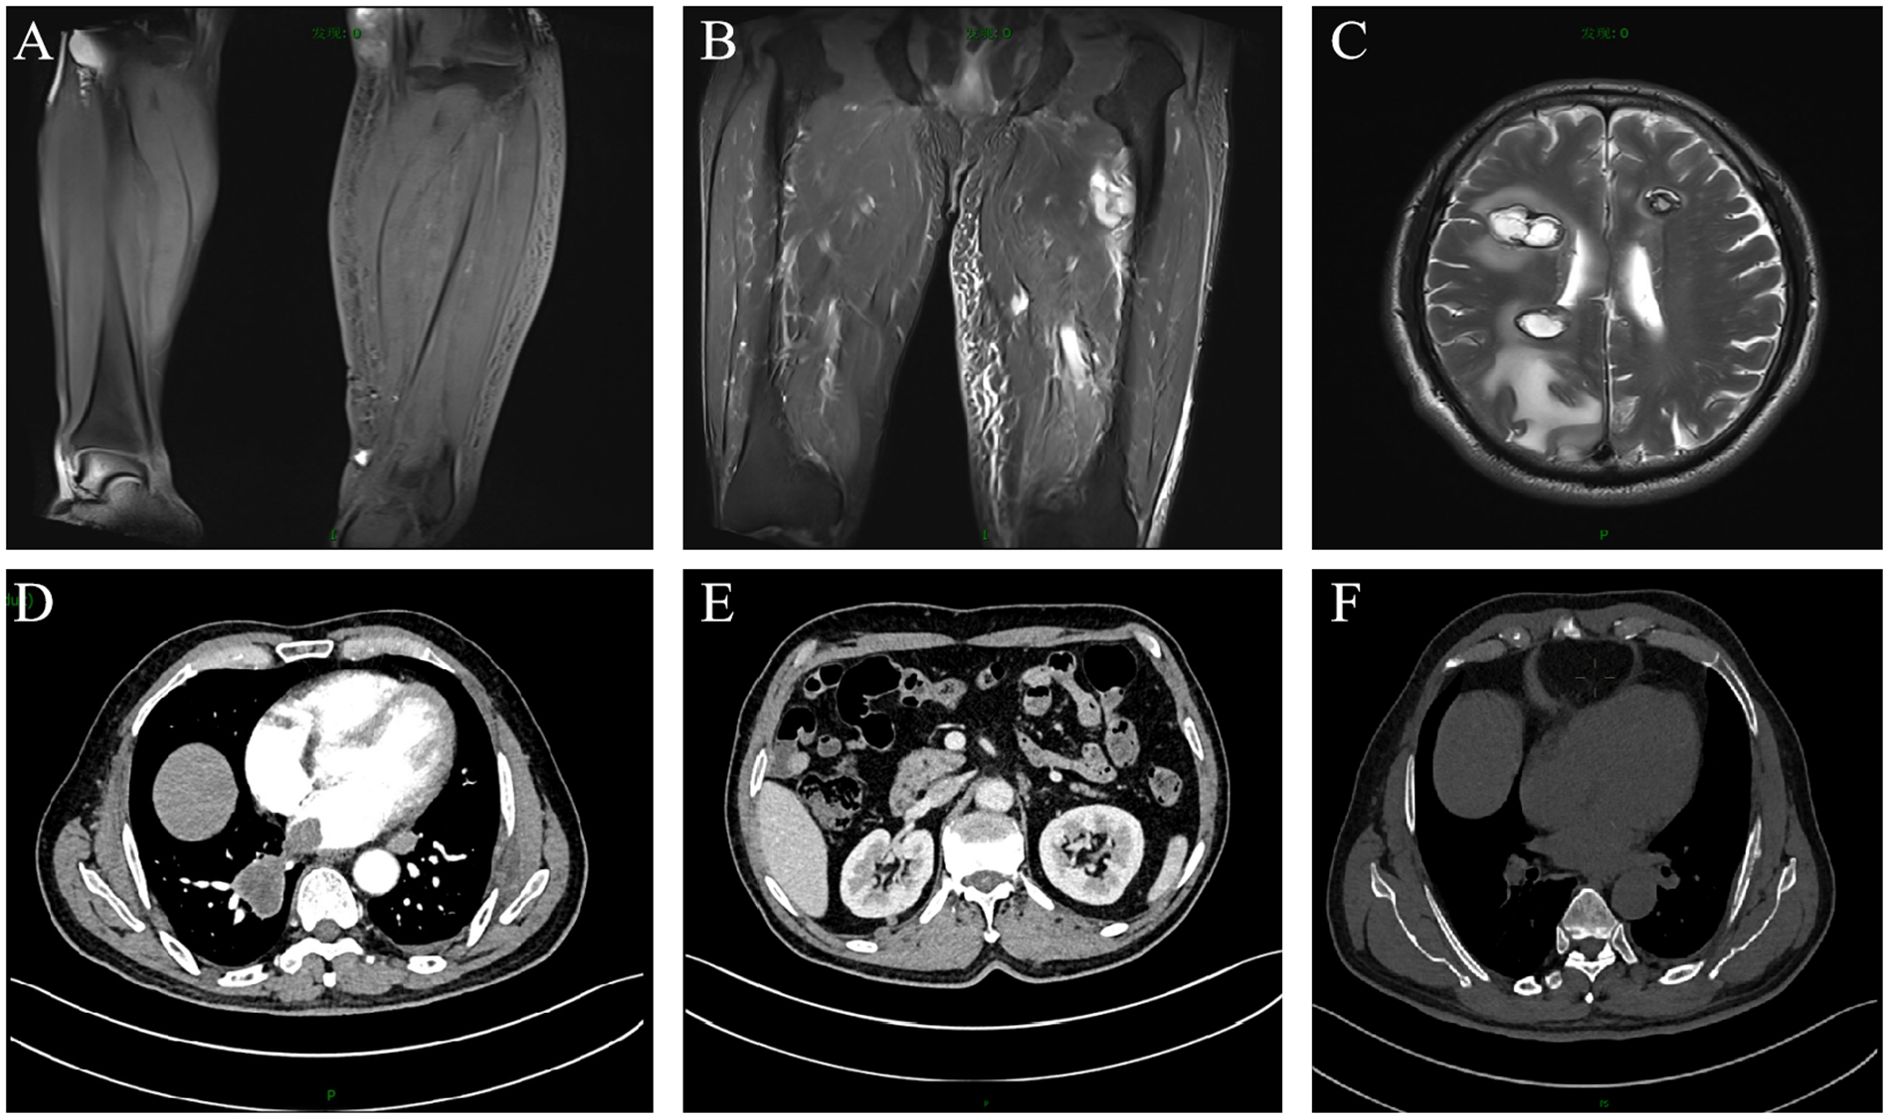

A 67-year-old male patient presented with melanoma of the left lower limb (Figure 1), accompanied by multiple systemic metastases, including those in the brain, lungs, pericardium, kidneys, and bones, and sought medical observation at our hospital (Figure 2). Three years prior, he underwent surgical resection and was subsequently diagnosed with wild-type BRAF V600E through pathological examination. He is currently undergoing regular immunotherapy with trastuzumab. Over the past year, the patient has reported a decrease in appetite but has not experienced any abdominal symptoms such as pain, nausea, vomiting, bloody stools, weight loss, or anemia. During an upper gastrointestinal endoscopy, a mass was identified on the posterior wall of the gastric fundus and the greater curvature of the upper stomach, with melanin deposition observed on the surface (Figures 3A, B). Additionally, four masses were detected on the anterior wall and descending segment of the duodenal bulb, also exhibiting surface melanin deposition (Figures 3C, D). Consequently, a histological examination of the masses located in both the stomach and the duodenal bulb was deemed necessary. Histological examination using hematoxylin and eosin staining revealed numerous tumor cells of varying sizes with prominent nucleoli in the local gastric mucosal tissue, alongside some cells containing visible melanin granules (Figure 4A). High magnification analysis of the duodenum also identified a small quantity of pigments in the localized area, which are characteristic features of melanoma (Figure 4B). Immunohistochemical analysis demonstrated positive expression for S100, MelanA, and SOX10 (Figures 5A–C), while CK and CAM5.2 the result turns out negative (Figures 5D–F). The Ki67 proliferation index was 90%, aligning with the diagnosis of metastatic malignant melanoma. The patient declined additional treatment and was subsequently discharged.

Figure 2. Enhanced magnetic resonance imaging and computed tomography scans of the patient. Metastatic lesions in the: (A) left calf; (B) left thigh; (C) brain; (D) lungs and pericardium; (E) kidneys; (F) bones.